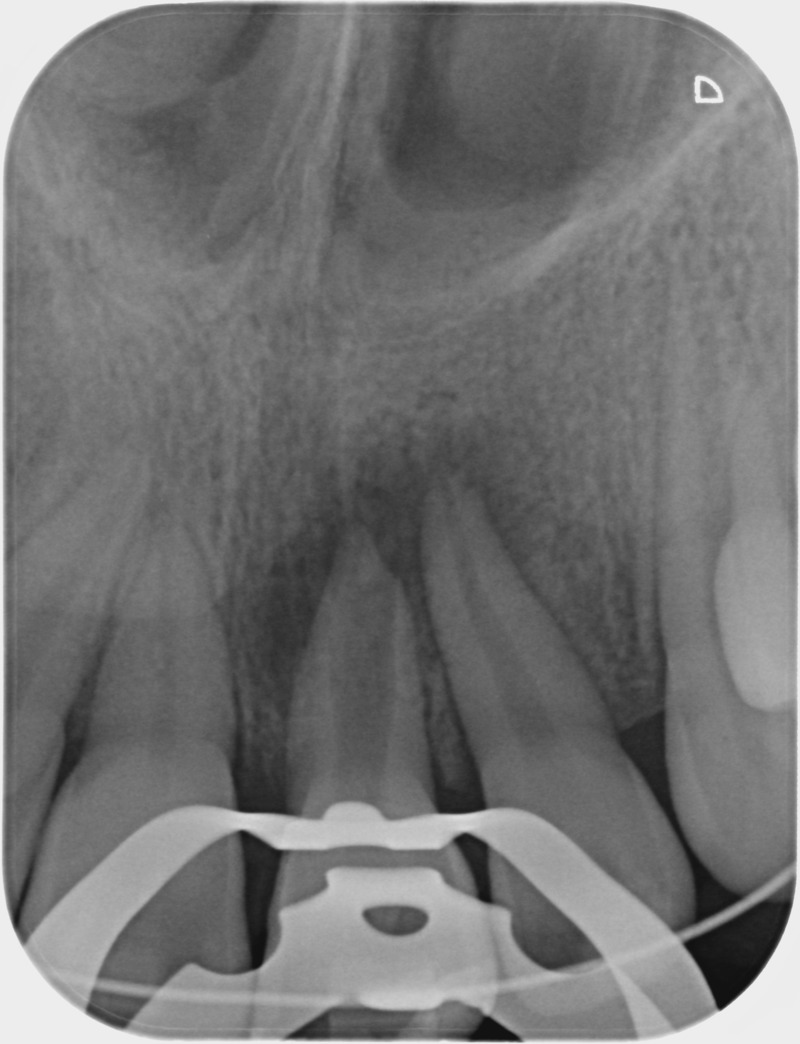

• Traitement endodontique : Sous anesthésie locale et à travers la protection d’un champ opératoire nous accédons à la pulpe de la dent à soigner, puis aux canaux de ses racines que nous devons désinfecter. Ce soin nécessite l’élimination complète de la source de contamination (souvent la carie) parfois sous une ancienne reconstitution ou une couronne qu’il faut alors retirer. Une fois le nettoyage et la mise en forme des canaux réalisés, nous les obturons de façon hermétique avec un ciment et un matériau thermoplastique appelé Gutta Percha. Ceci afin d’empêcher une nouvelle prolifération bactérienne et d’assurer le maintien de la dent dans ses structures de soutien (ligament parodontal et os alvéolaire). L’ouverture effectuée au centre de la dent sera d’abord refermée avec un pansement provisoire avant d’envisager ensemble la reconstitution d’usage : un composite, un inlay-onlay ou une couronne.

Après